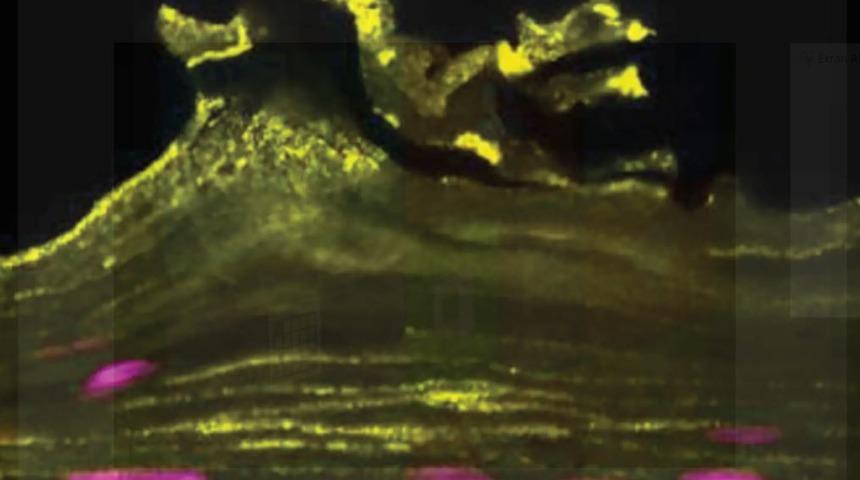

(Fotoğraflar: Harvard Üniversitesi)